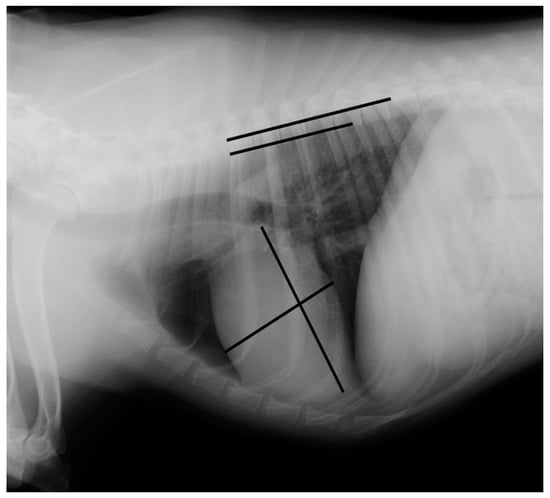

Measurements were made using an adjustable calliper in millimetres, which was then converted to vertebral units (v) exact to 0.1 v, according to the method described by Buchanan and Bucheler [4]. All of the measurements were performed by the same examiner (EC) using DICOM PACS view radiography computer software (Synapse, Fuji, Tokyo, Japan). In the right lateral radiograph, the long axis of the heart was measured from the ventral border of the left main stem bronchus to the most distant contour of the cardiac apex (L). The maximal short-axis of the heart was measured perpendicular to the long-axis (S). The two measures were repositioned over thoracic vertebrae beginning with the cranial edge of T4, using an adjustable calliper (Figure 1 and Figure 2).

Figure 1. Measurement of the vertebral heart scale in a right lateral radiograph illustrating an example of a vertebral heart scale in a Brittany Spaniel of 10.8 v (the image was acquired using a PICKER CONVIX 80–UNIVERSIX 120 device (Picker International, Uniontown, OH, USA); the kVp, mA, and time settings were not recorded). Two lines are drawn on the heart to measure its long and short axes. They are then transposed onto the spine and recorded as the number of vertebrae beginning with the cranial edge of T4. These values are estimated to one decimal place and added to obtain the vertebral heart size.